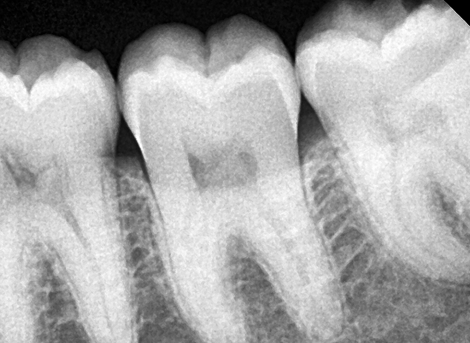

Diagnosis & Preparation

Rubber-dam isolation for hygiene

Advanced anesthesia for a painless experience